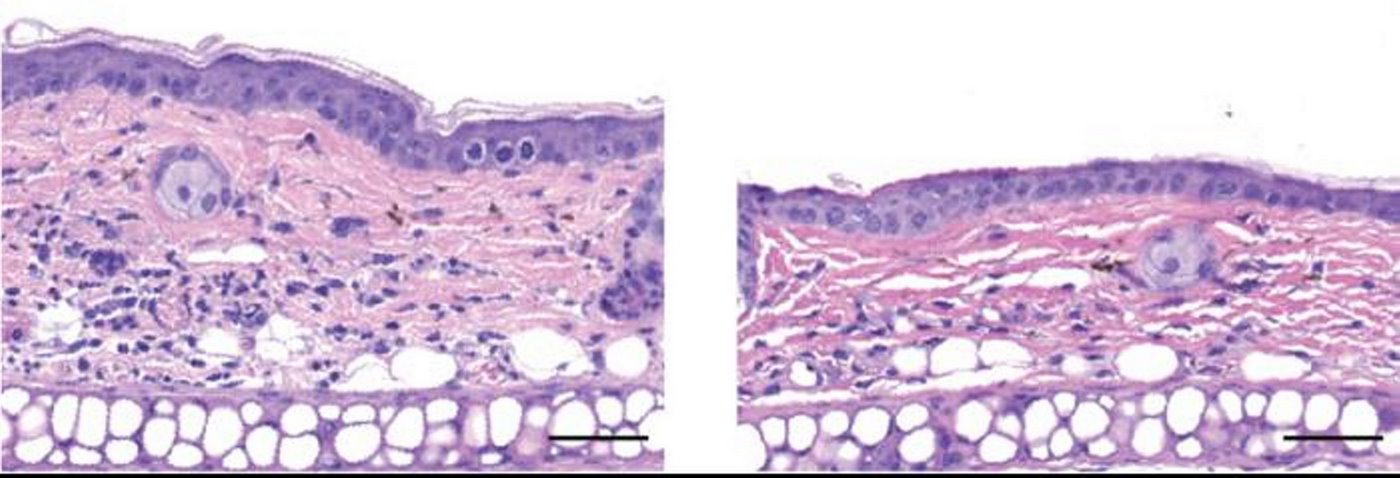

They found that SYM2081 effectively suppressed mast cell degranulation and proliferation in both mice and human skin samples. When the mice received a topical cream containing SYM2081 before the induction of rosacea or eczema-like symptoms, skin inflammation and other symptoms of disease were much milder.

A daily cream containing a GluK2-activating compound could therefore be a promising way to prevent rosacea and other inflammatory skin conditions.